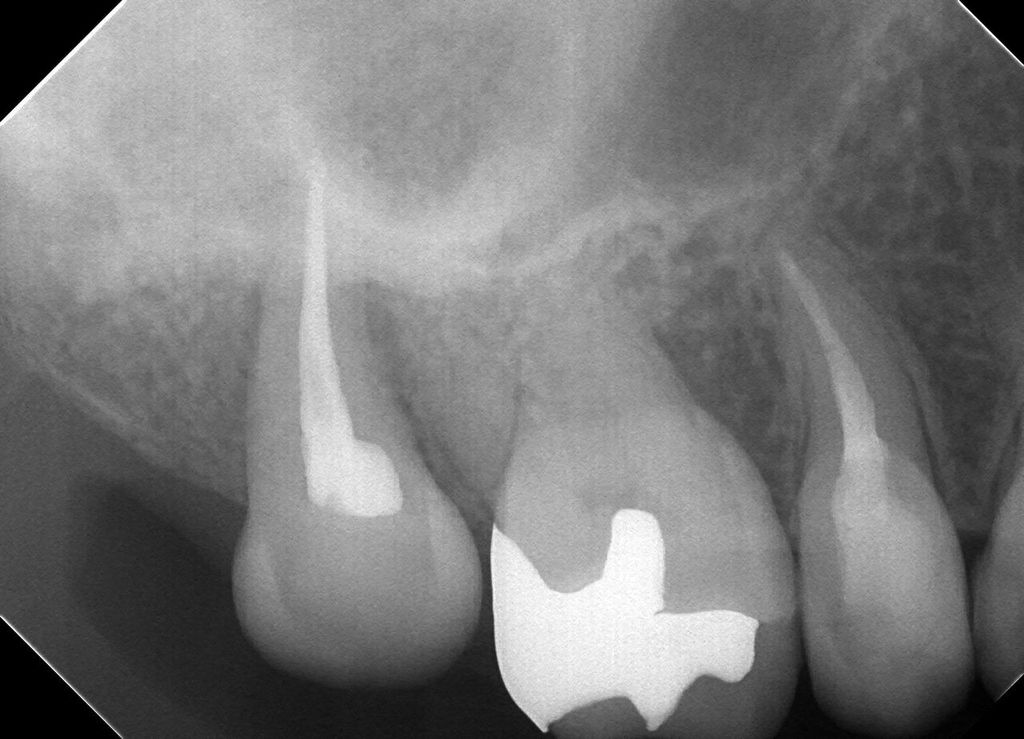

その後経過をみて根っこの治療をして最終的なお薬を詰めた状態です。